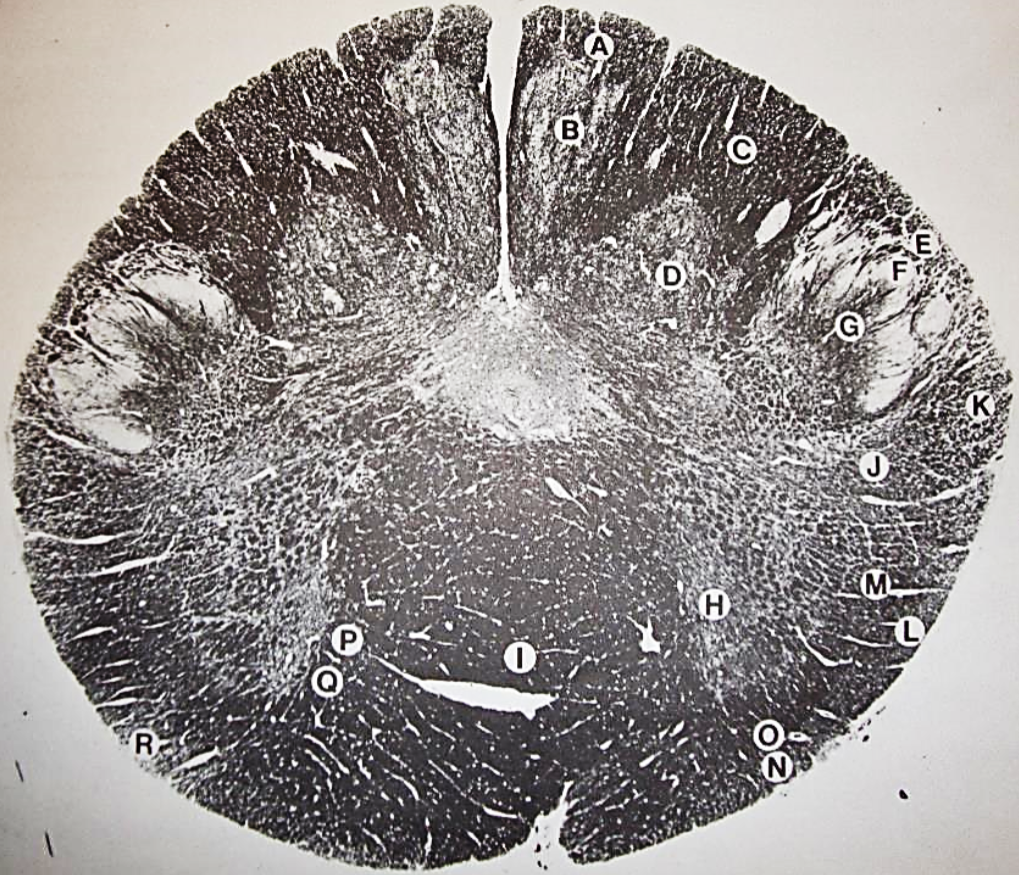

A

fasciculus gracilis

B

gracile nucleus

C

fasciculus cuneatus

D

cuneate nucleus

F

internal arcuate fibers

G

decussation of internal arcuate fibers

H

medial lemniscus

I

hypoglossal nucleus

J

dorsal motor nucleus vagus

K

solitary fasciculus

L

solitary nucleus

M

dorsal longitudinal fasciculus

N

spinal trigeminal tract

O

spinal trigeminal nucleus

P

posterior spinocerebellar tract

Q

anterior spinocerebellar tract

R

spinal lemniscus

S

lateral vestibulospinal tract

T

rubrospinal tract

U

lateral reticular nucleus

V

medial accessary olivary nucleus

W

pyramidal (corticospinal) tract

X

arcuate nucelus

Y

medial longitudinal fasciculus

Z

tectospinal tract

a

fascicles of hypoglossal nerve